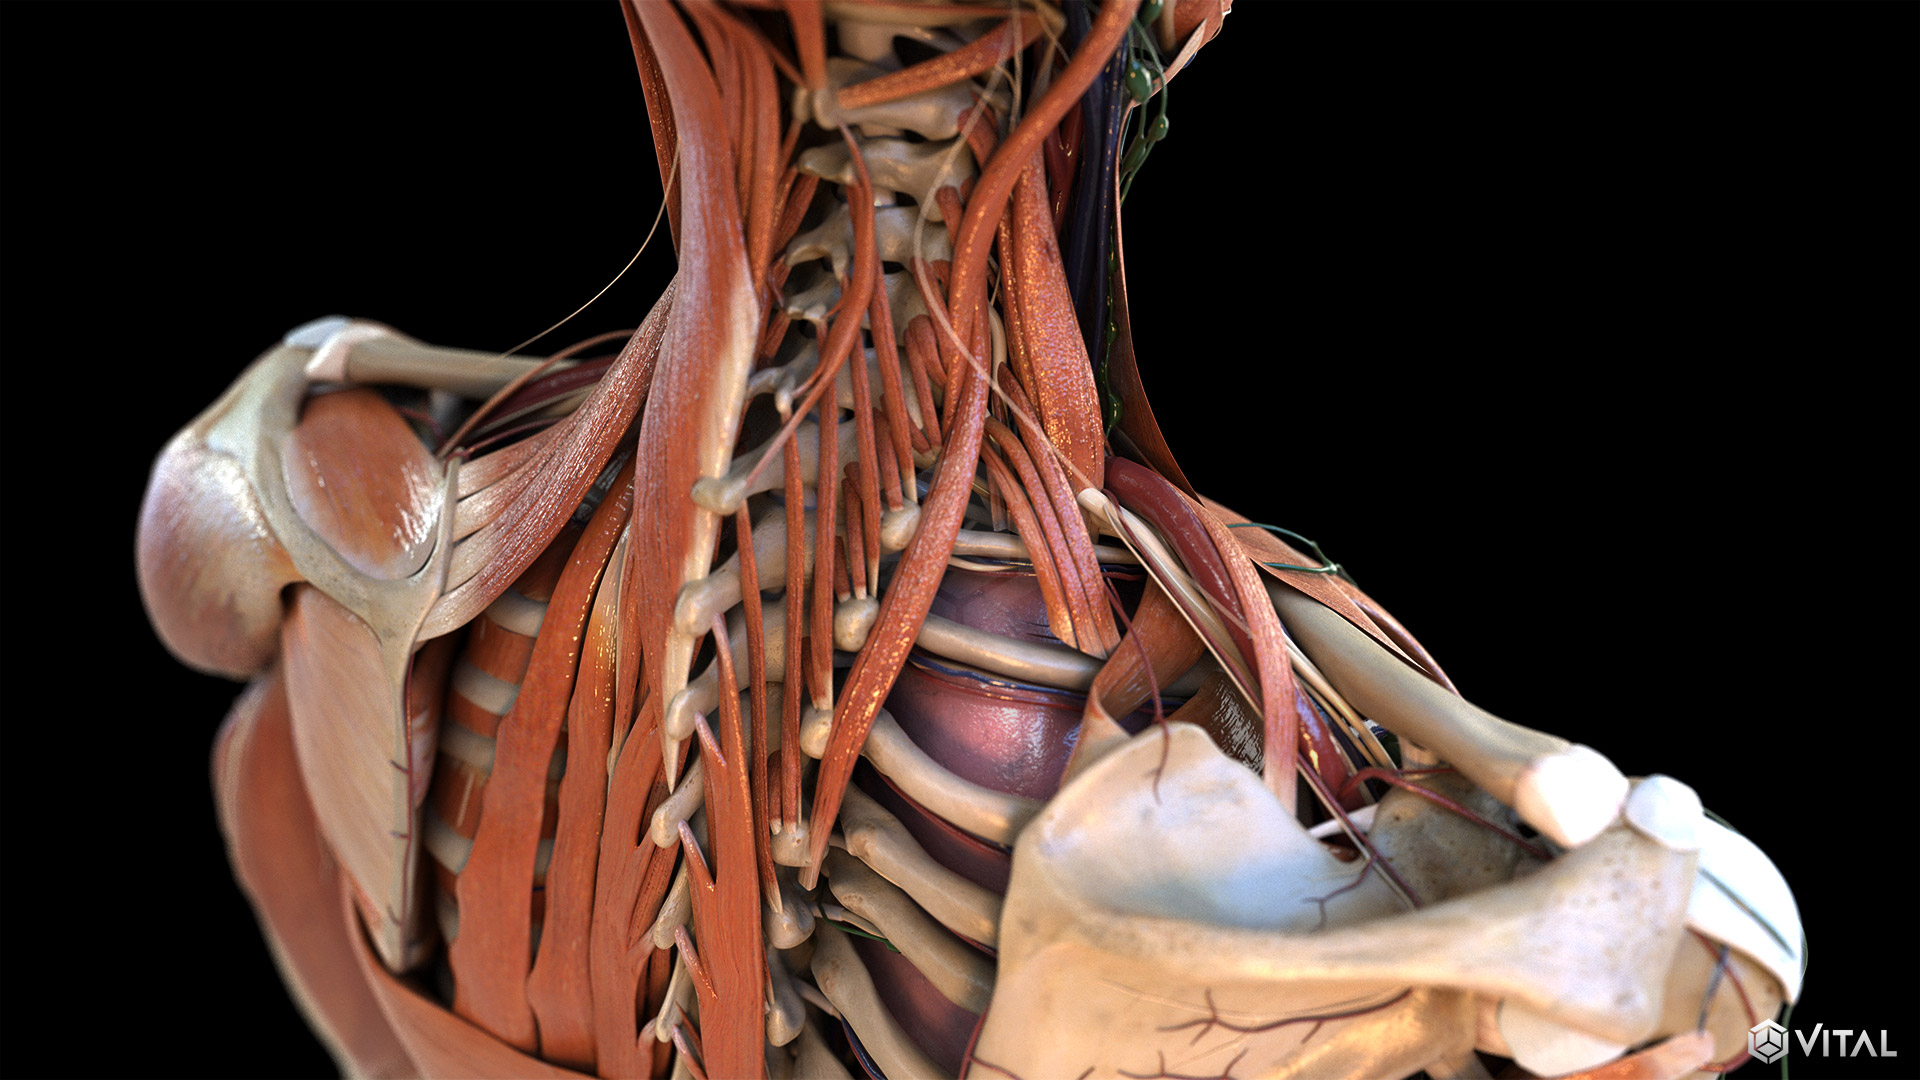

Medical

Vital and UET collaborate to support several clients throughout the medical industry. Together, we provide illustrations, animations, and trial exhibits to help depict complex anatomy and medical procedures clearly and precisely. We’re able to create an immersive, easy to understand learning experience, by combining real footage, such as captured ultrasounds, with correlating high fidelity 3D animation.